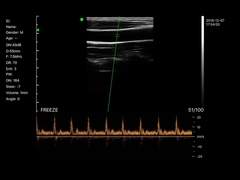

Wuxi Biomedical Technology Co., Ltd.

Kwaliteit Draagbare ultrasone Scanner, handbediende Ultrasone klankscanner Fabrikant uit China